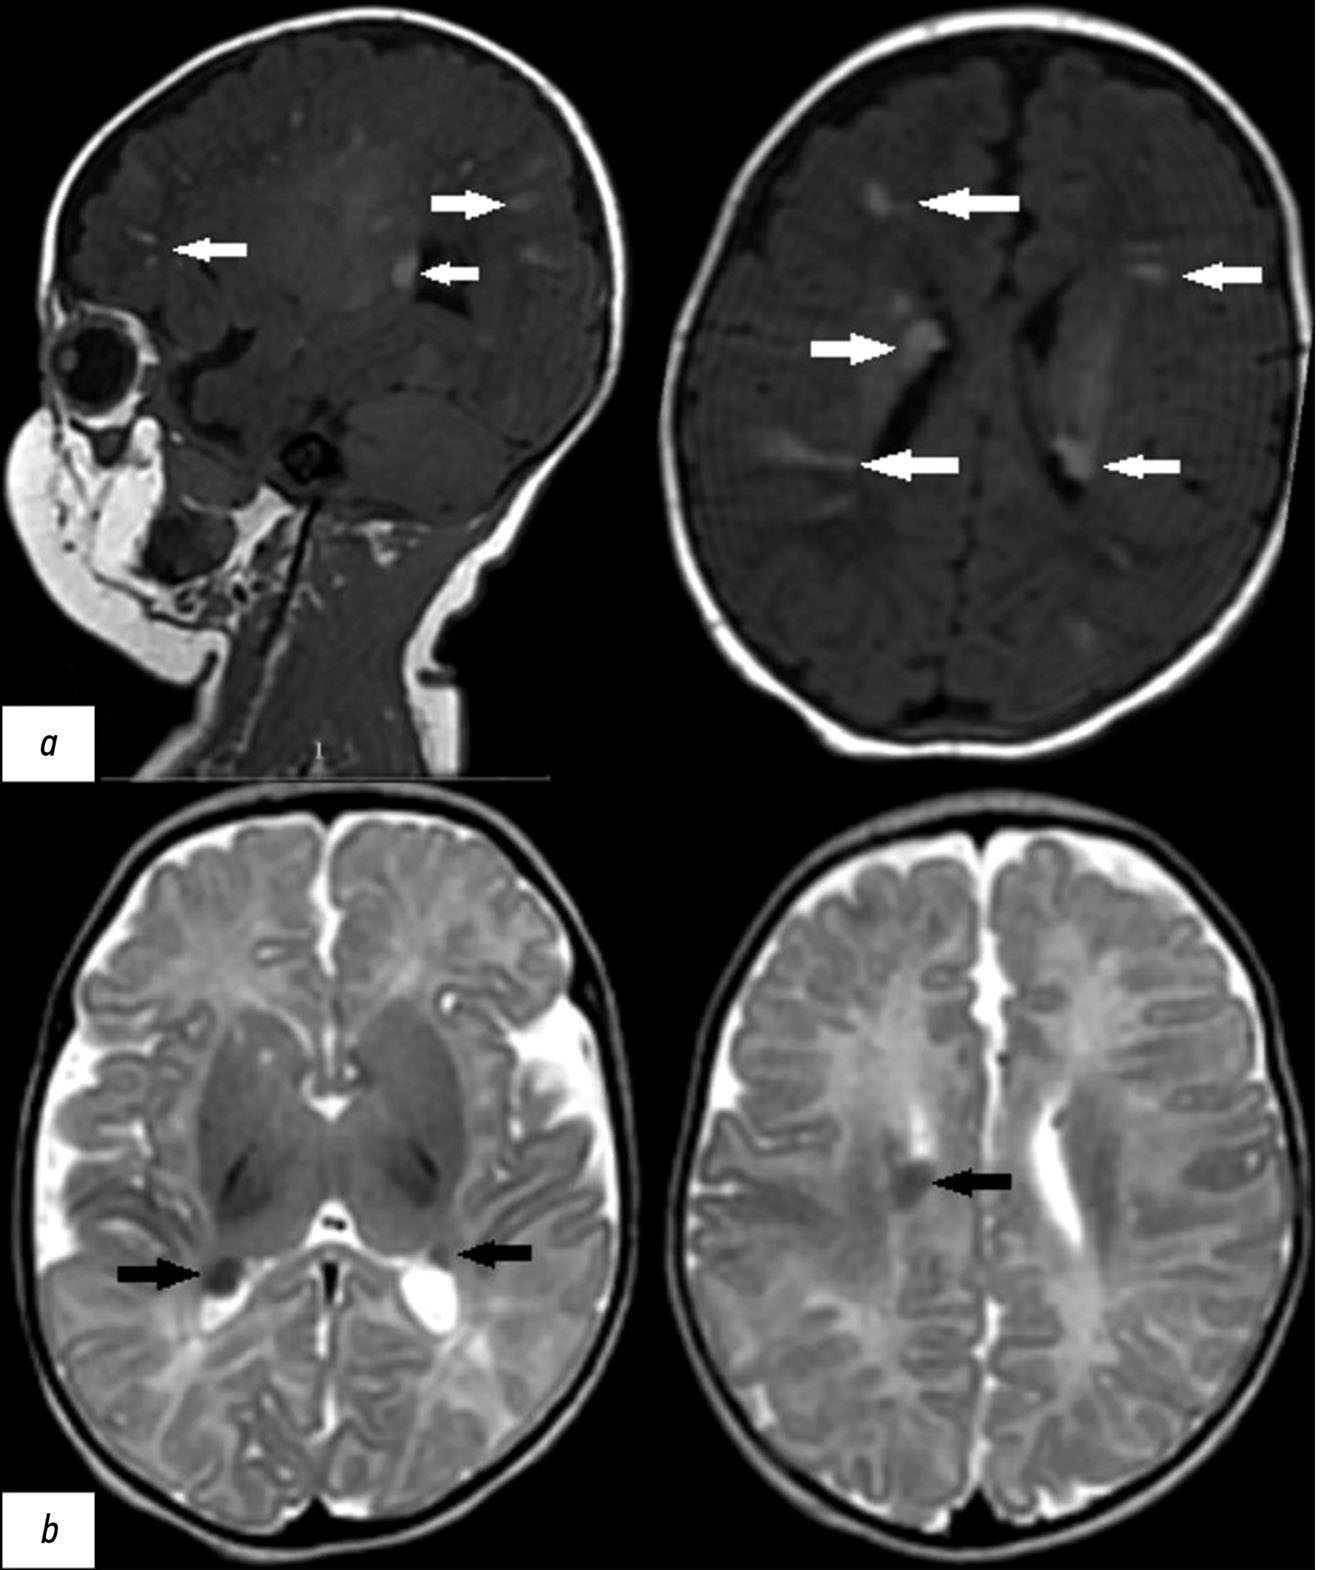

Рис. 2. Результаты пренатальной магнитно-резонансной томографии грудной клетки плода в аксиальной плоскости с использованием Т2-взвешенной последовательности (T2 Ax CHEST). III триместр беременности (срок 29 нед. и 4 дня). В левом и правом желудочке сердца определяются образования с аналогичными паттернами, характерными для рабдомиомы (белые стрелки).

В головном мозге по контурам боковых желудочков выявлены разнокалиберные субэпендимальные узелки с гипоинтенсивным сигналом на Т2-ВИ и гиперинтенсивным — на Т1-ВИ (рис. 3). Других патологических изменений у плода по результатам МРТ не выявлено.

Рис. 3. Результаты пренатальной магнитно-резонансной томографии головного мозга плода в III триместре беременности (срок 29 нед. и 4 дня): а — наличие субэпендимальных гипоинтенсивных очагов на Т2-взвешенном изображении (чёрные стрелки); b — наличие субэпендимальных гиперинтенсивных очагов на Т1-взвешенном изображении (белые стрелки).